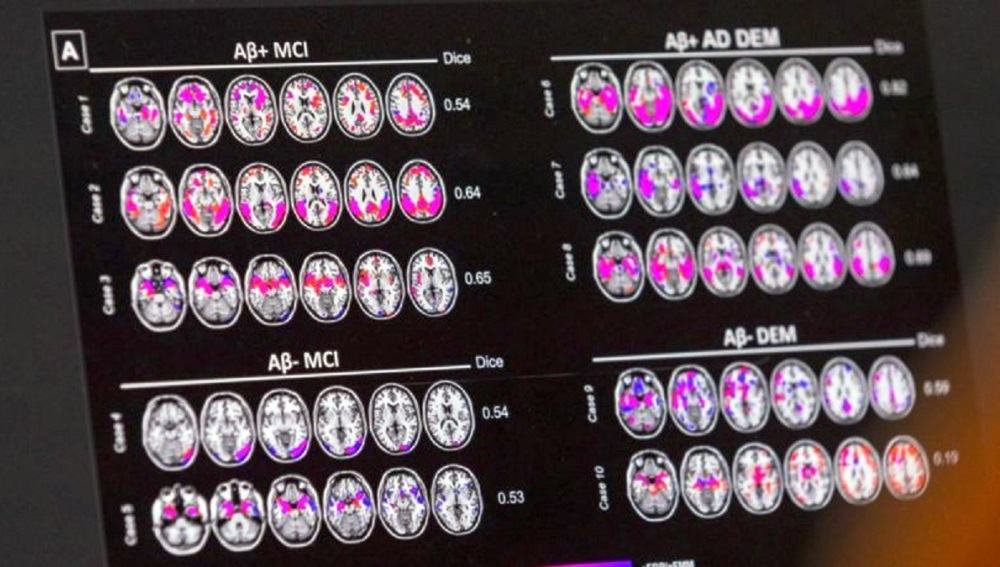

Hasta insanların beynine yakından bakıldığında amiloid ve tau adlı proteinlerin anormal bir biçimde birikmeye başladığı görülüyor.

Bulgularına göre Alzheimer hastalarının beynindeki nöronların arasında anormal miktarda amiloid plakları ve tau düğümleri oluşuyor. Bu da beyin ödemine neden oluyor. Ödem, nöronların içindeki kimyasal dengeyi bozuyor.

Plak ve düğümlerin oluşumuyla birlikte beyin hücreleri MEG3 adlı bir özel bir molekül üretiyor. MEG3 molekülü nekroptoz yani hücre intiharlarını tetiklediği için süreçte kilit rol oynuyor.